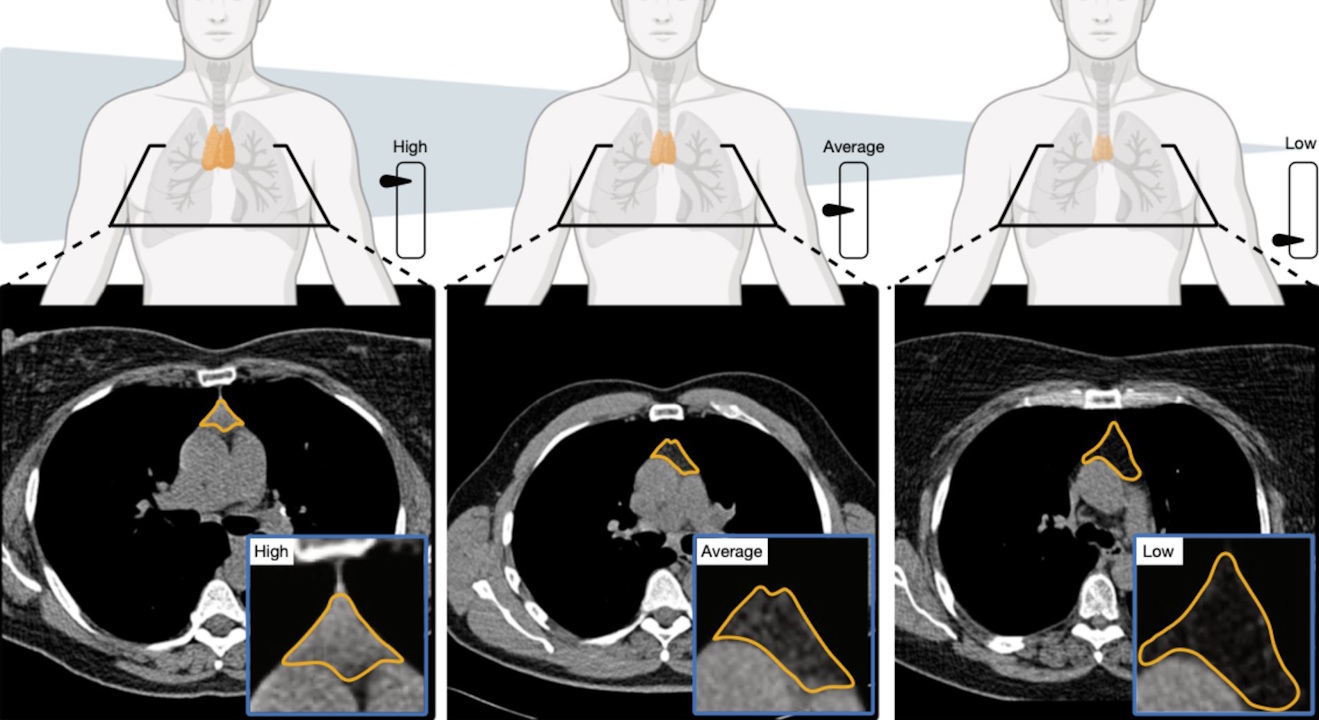

Схема та знімки комп'ютерної томографії в людей із гарним здоров'ям тимуса (зліва), нормальним (посередині) і поганим (справа). Mass General Brigham / Nature

Попередні дослідження вже вказували на те, що тимус зберігає свою важливість і в дорослому віці: його видалення пов’язали з вищими ризиком раку та смертністю. Нове дослідження провели на двох вибірках: 25 тисячах учасників програми скринінгу раку легенів і 2500 здорових добровольцях. Їм проводили комп’ютерну томографію грудної клітини, де знаходиться тимус, а потім за розміром, формою та внутрішньою будовою органа науковці оцінювали його здоров’я.